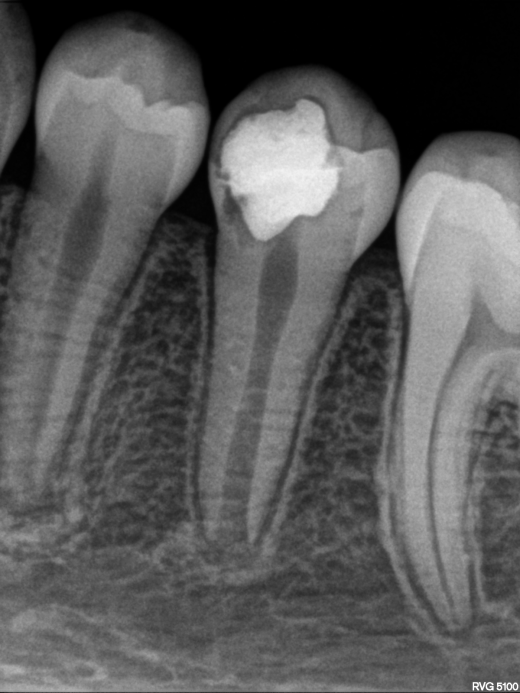

Caso clínico Molar